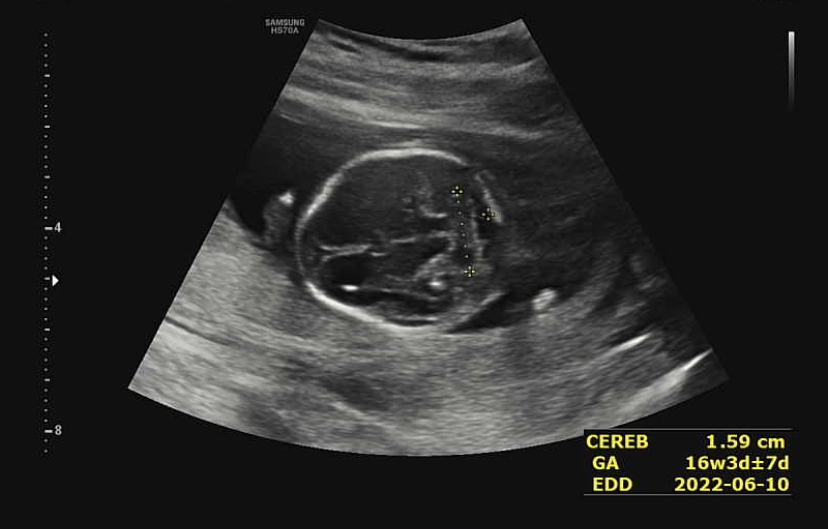

제일 먼저 본 머리! 뇌가 잘 정착해서 성장하고 있다고 하셨다. 뇌 중간 부분의 길이도 재줬는데 어떤 부위였는지는 잘 기억나지 않는다^^;처음 듣는 부위였던 것 같다.